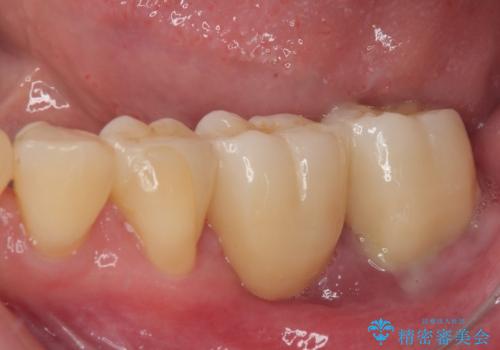

全顎的な治療後に、急遽ニューヨークへ転居されることとなったのですが、治療後から経過観察を行っていた右上犬歯が歯肉縁下に及ぶむし歯のため、クラウンが土台ごと外れてしまったとの連絡がありました。

他の部位にインプラント治療を行っていたことから、こちらの歯に対してもインプラントによる補綴治療を希望されたため、1泊での帰国時に抜歯、インプラント埋入、仮歯の装着を行い、数ヶ月後の帰国時にオールセラミッククラウンの型取りと装着を行う計画としました。

インプラント埋入時は1泊、補綴治療時には3週間ほど日本に滞在していただき、2回の渡航で無事に治療を終えることができました。